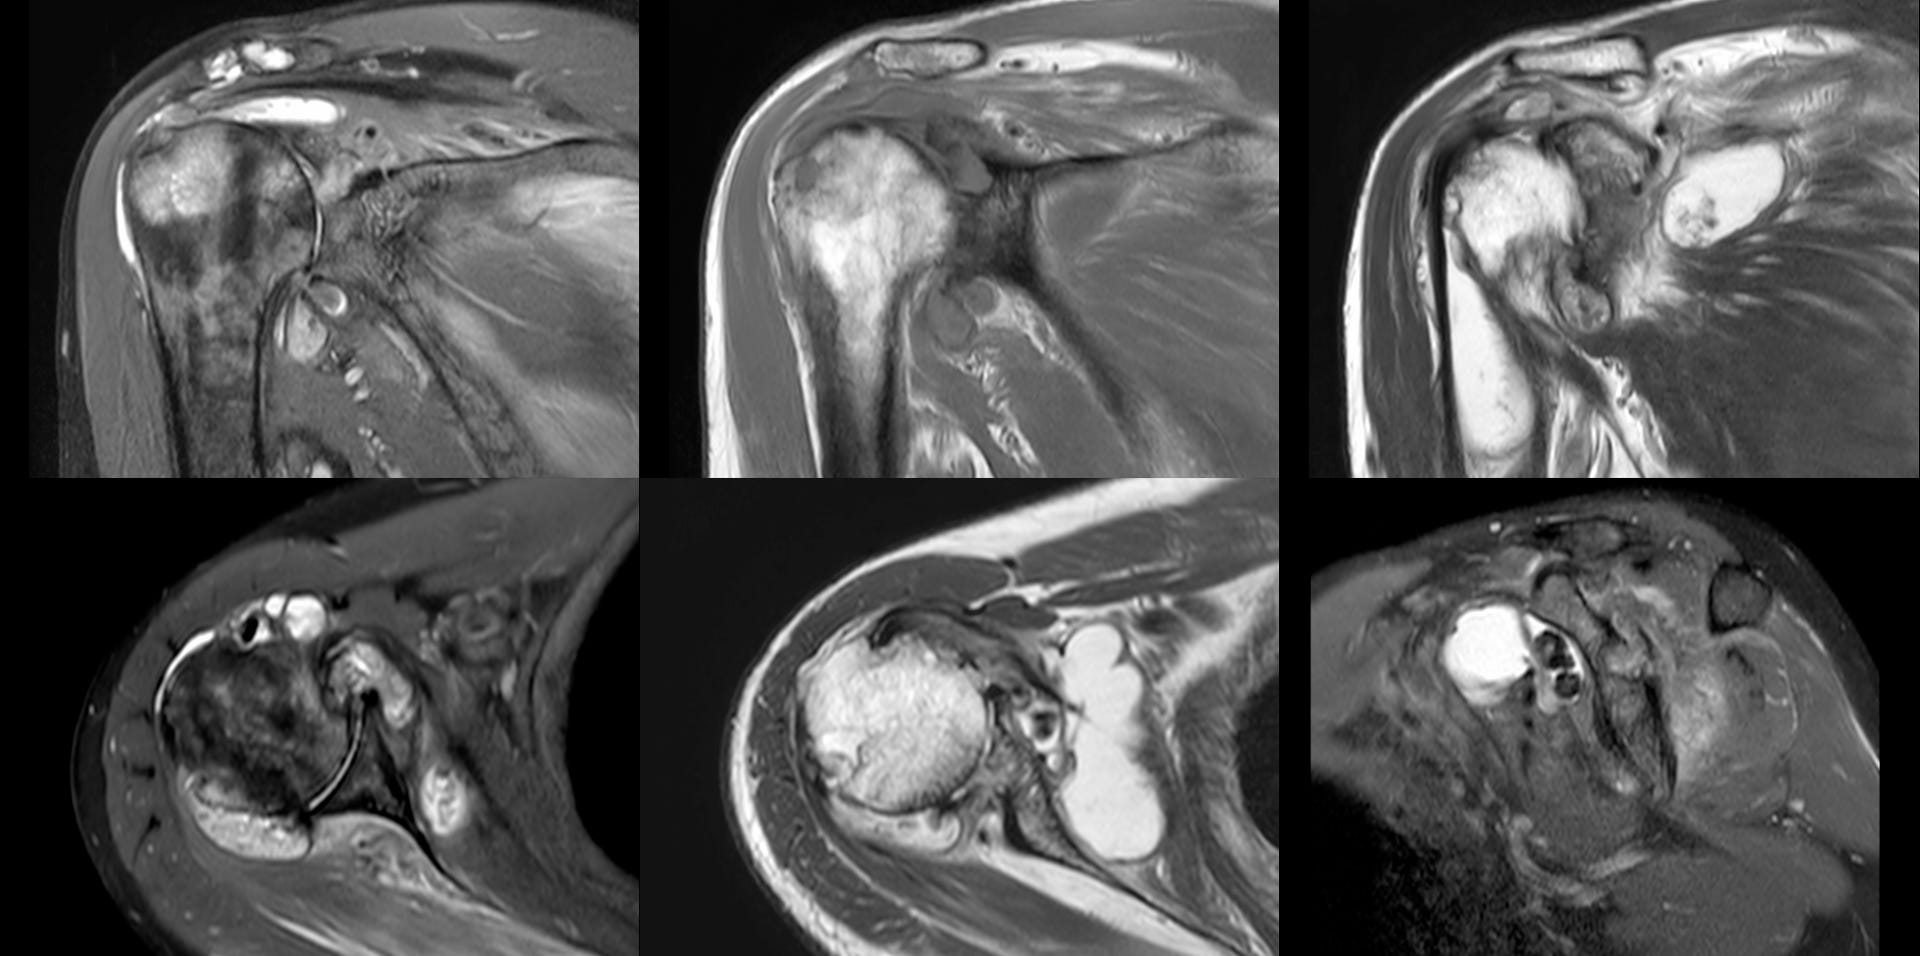

MRI showed a destructive arthropathy, as did a CT scan. Neuroarthropathy was ruled out with an MRI cervical spine.

The video describes the findings and the final diagnosis obtained on USG guided aspiration.